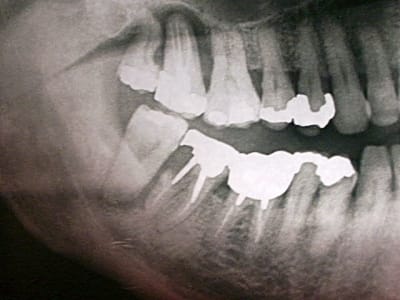

patient, 65 ans, ami proche de la famille, pére d'un très bon ami d'enfance.

douleurs récurrentes au maxillaire droit à la mastication.

sensations de dents + ou - mobiles au max D et mand G.

Habitudes: visite annuelle chez son CD. a effectué les soins et prothèses conseillés. Pas de gros travaux entrepris depuis 20 ans. utilise un hydropulseur en plus du brossage (mais ne sait surement pas que son efficacité sur la PD est nulle).

Dernière visite chez son CD: 3 mois... pour la même raison. RAS tout va bien (???) + un ATB et roule ma poule... (???).

n'a plus trop confiance dans son CD...

motivation: ok. prêt à faire des kms pour venir me voir. prêt à faire de gros rdv (2H).

Je l'ai envoyé faire une pano en attendant de le voir en consultation. Bigre!!!!

premières impressions?

Manifestement alvéolyse horizontale généralisée, 25% de perte d'attache à 65 ans : je penche pour une parodontite chronique de l'adulte.

Je soupçonne aussi un trauma occlusal.

Je ne doute pas que tes talents en endo permettront de sauver ce qui l'est (bonne chance pour 36).

Mais 47 est HS.

Ouais, l'usure occlusale est quand même flagrante.

Implant sur 47 et je crois que je me séparerais des sagesses, z'ont pas l'air catholiques.

moi, c'est la 17 qui me chagrine le plus.

la racine distale de 47 est morte. Première impression: la virer, garder la racine M, petit bridge pro en résine renforcée en attente de stabilisation du pb paro et assurer calage de 48. Voir par la suite pour implant ou bridge.